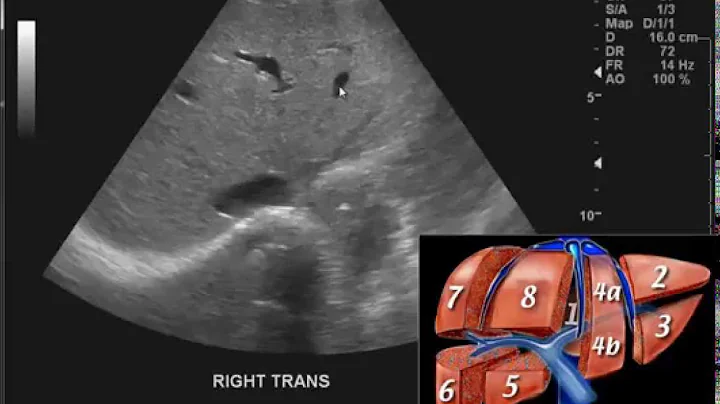

Basic Ultrasound Scanning Technique and scan windows for an Abdominal Ultrasound.